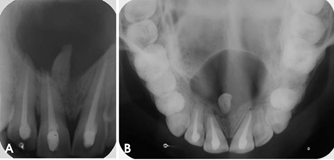

Khám lâm sàng thấy chậm mọc răng so với tuổi mọc dự kiến. Chẳng hạn như tuổi dự kiến mọc răng cửa giữa hàm trên vào khoảng 7-8 tuổi. Khi đến độ tuổi này nếu cả hai răng chưa mọc hoặc đã mọc một răng trong khi răng đối xứng chưa mọc hoặc mọc chậm thì nghi ngờ khả năng có răng thừa ngầm gây cản trở sự mọc răng. Hoặc phát hiện khe răng thưa răng cửa hàm trên hoặc có bất kì sự mọc lệch lạc nào của răng cửa hàm trên đều cũng nên chụp XQ kiểm tra sự hiện diện của răng thừa. Việc chẩn đoán bằng XQ là rất quan trọng. Tại BV Đa khoa Tỉnh Quảng Trị có đầy đủ các phương tiện chẩn đoán như XQ cận chóp, XQ răng toàn cảnh và đặc biệt là phương tiện chụp cắt lớp vi tính chùm tia hình nón (CT Cone Beam) có thể phát hiện răng thừa theo 3 chiều không gian mà các phương tiện khác có thể không phát hiện ra. Minh họa trường hợp cháu trai 8 tuổi sau đây là một ví dụ.

Răng thừa (b) mọc trong vòm miệng khiến cho R22 (a) mọc lệch xoay trục XQ răng toàn cảnh không thấy răng thừa do R21 (a) che khuất,(b) là R22 bị xoay trục

Hình ảnh răng thừa (a) xuất hiện rất rõ trên CT Cone Beam, (b) là hình ảnh R21

Hình 3: Tính ưu việt của CT Cone Beam trong chẩn đoán răng thừa

(Nguồn: Bệnh viện Đa khoa Tỉnh Quảng Trị)